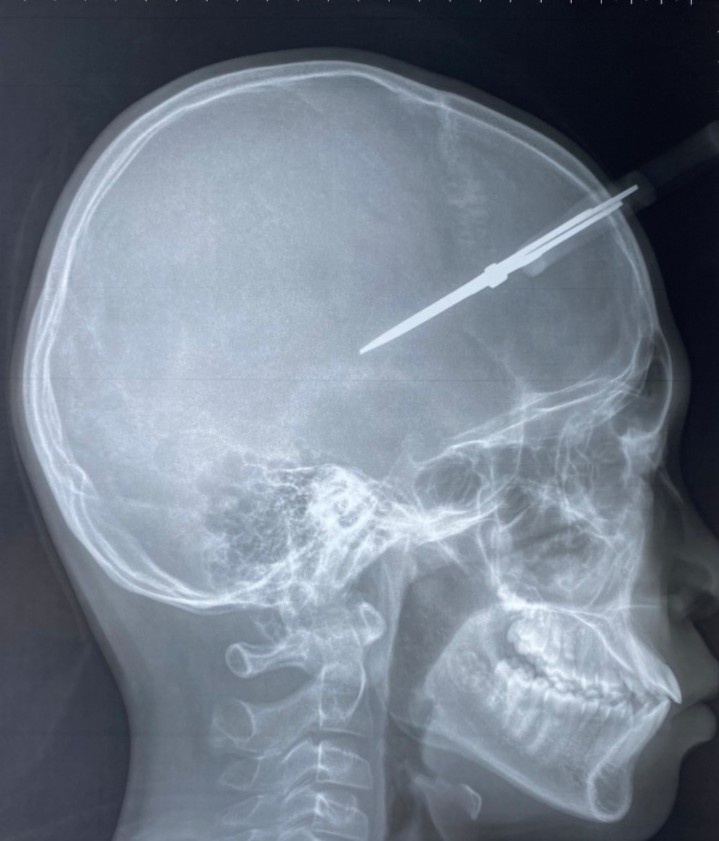

Theo thông tin khai thác, tai nạn xảy ra trong ngày đi học cuối cùng trước kỳ nghỉ Tết, khi bé H. chơi đùa với bạn cùng lớp. Thời điểm nhập viện, bé tỉnh táo, chiếc kéo vẫn cắm chặt vào đầu ở vùng thái dương phải. Phim chụp cho thấy cây kéo đã xuyên qua xương sọ, vào trong hộp sọ của bệnh nhi.

Cây kéo xuyên qua xương sọ của bệnh nhi. Ảnh: BVCC.

Ở tình huống này, vị trí của cây kéo nằm ở vùng thái dương, nơi có động mạch màng não giữa đi qua, rất có thể gây đứt động mạch, máu tụ ngoài màng cứng.